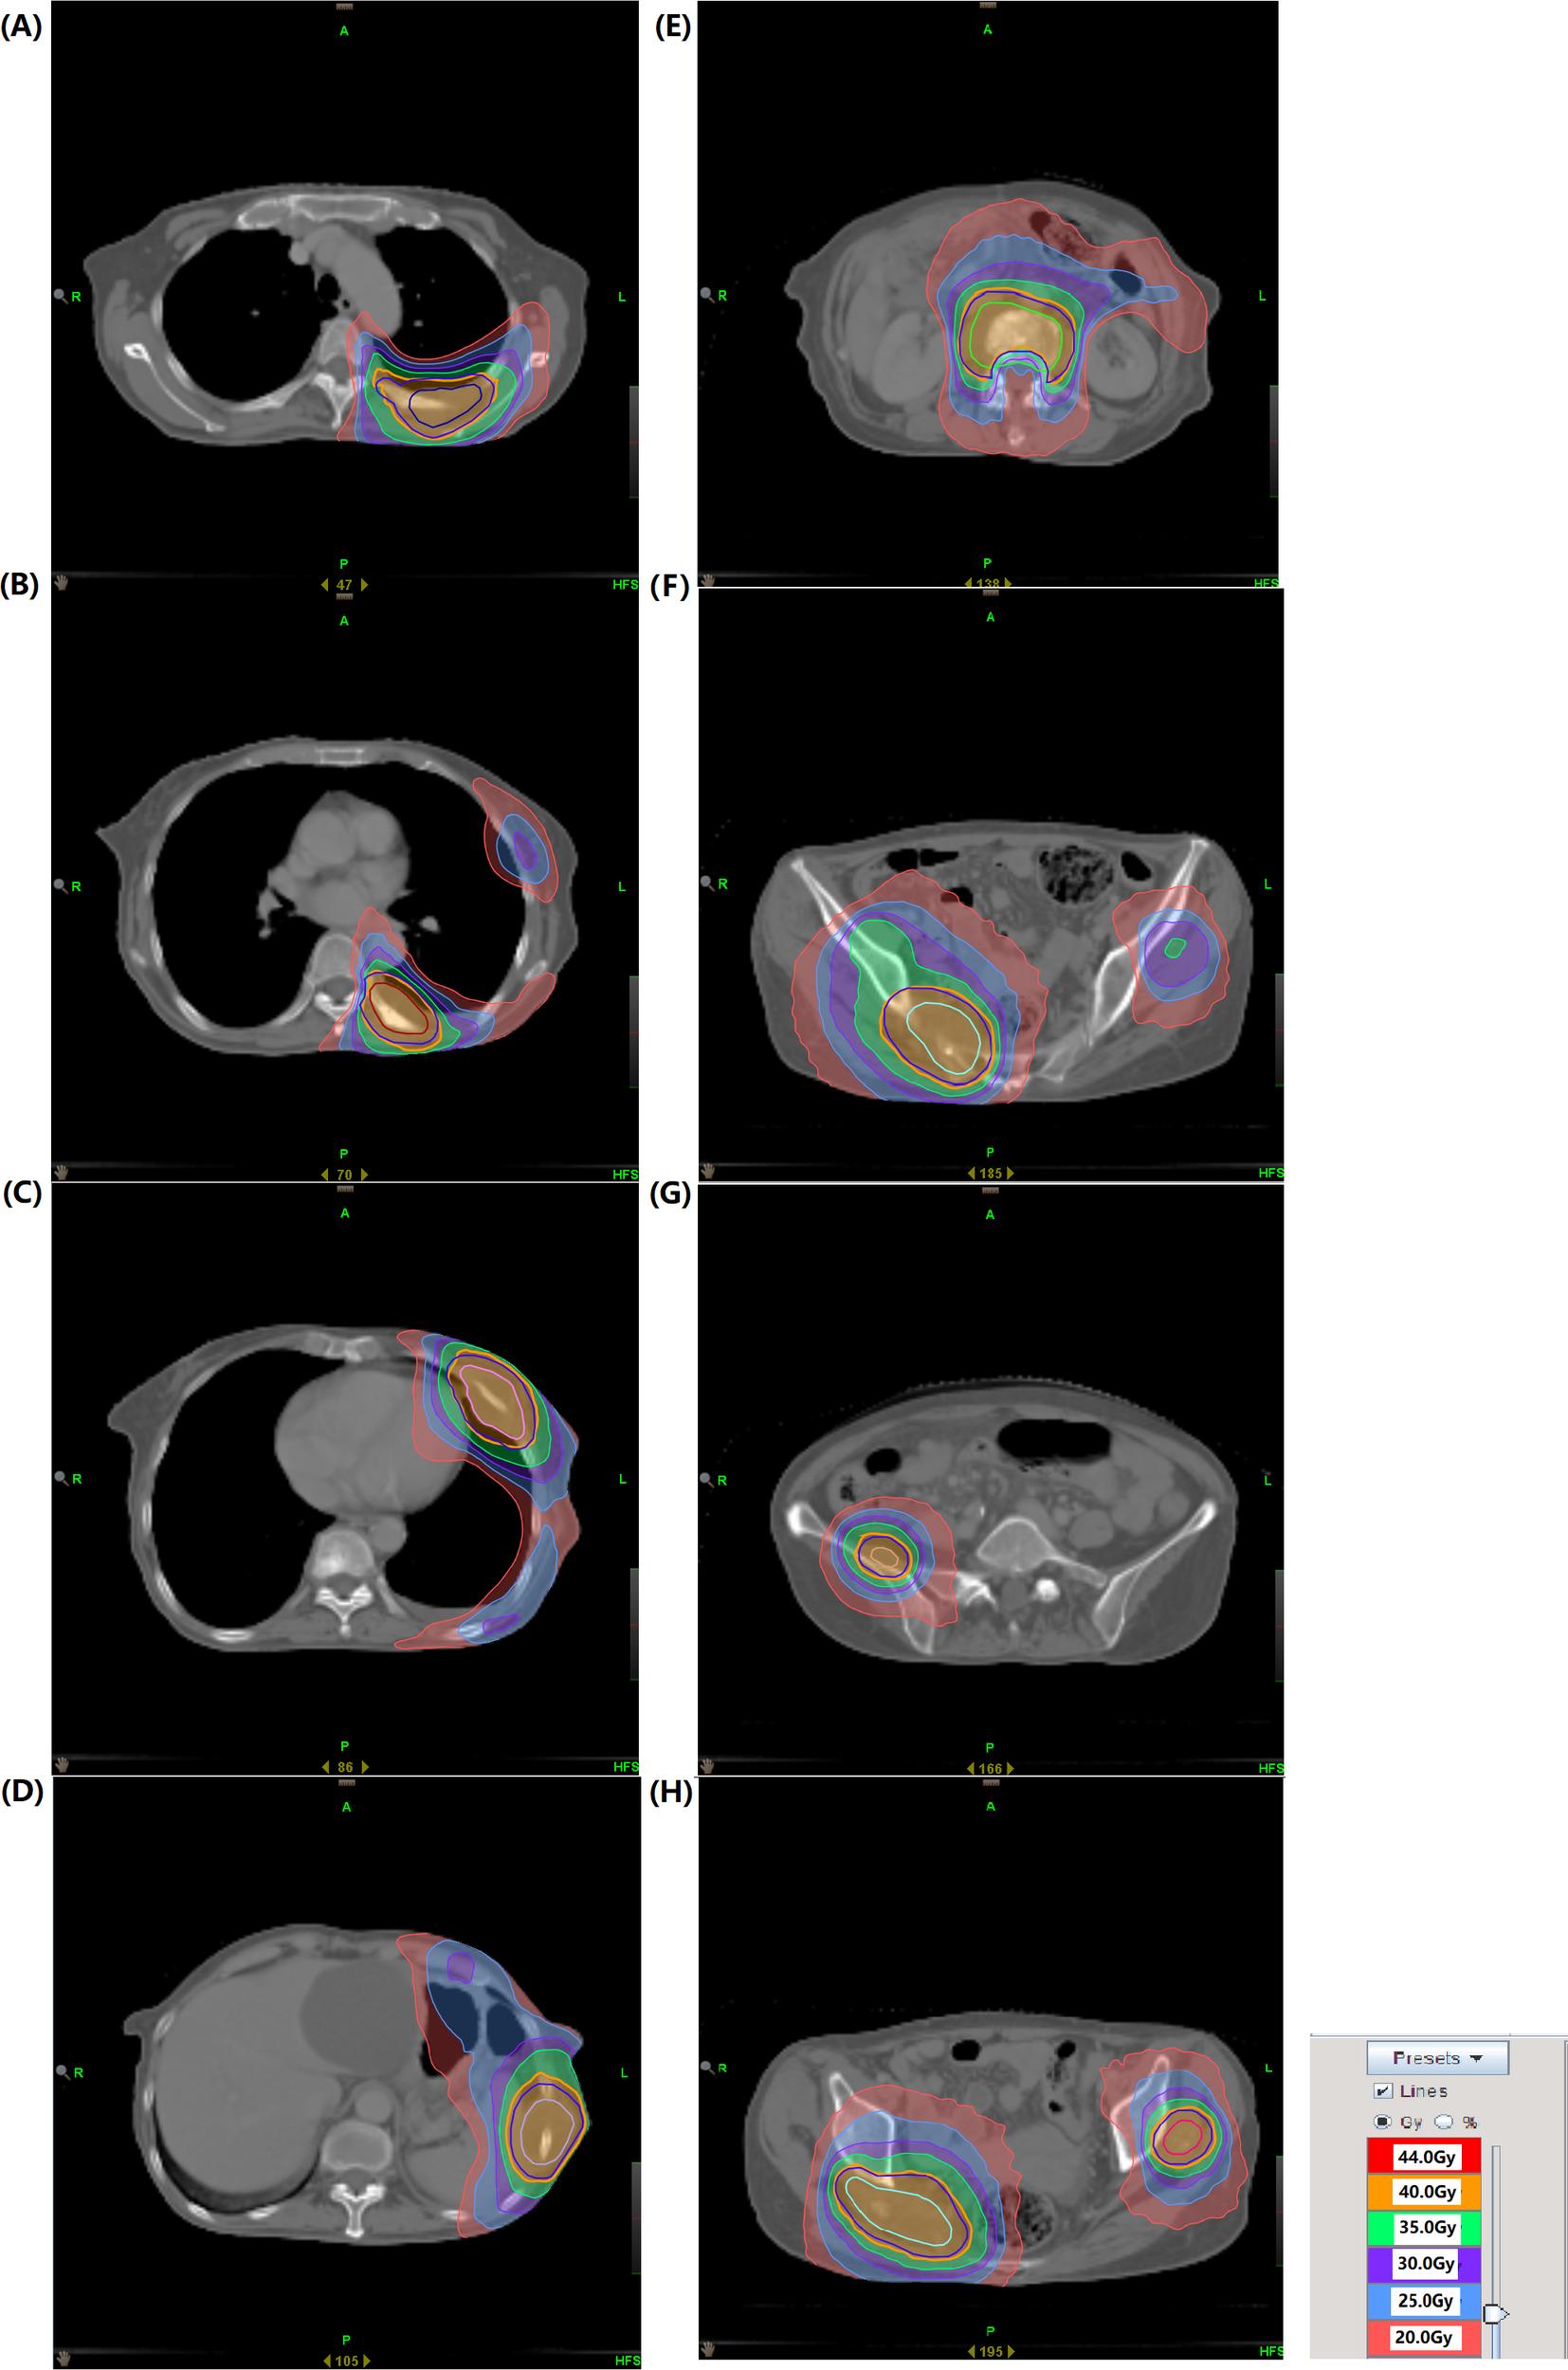

In May 2024, due to severe pain in multiple regions, including the left chest, right buttock, and right maxillofacial area, the patient sought palliative pain-relief radiotherapy. Imaging demonstrated multiple osseous and soft-tissue metastases throughout the body. The eight most painful lesions were treated, including the left ribs, vertebrae, right ilium, right piriformis, and left gluteus minimus, from June 7 to July 18, 2024 (Supplementary Figure 2). The representative dose distribution is shown in Figure 2. Given the patient’s poor performance status, we prescribed 40 Gy in 20 fractions. This regimen yields a BED similar to that recommended by the ASTRO guideline (29) for bone-metastasis radiotherapy, with a lower dose per fraction and thus fewer side-effects. However, only 19 fractions were completed due to the patient’s poor physical condition. Notably, the patient’s pain was significantly alleviated during treatment, and the left rib lesion visibly shrank. Tumor markers also gradually decreased (Figure 1). Remarkably, the radiotherapy induced an abscopal effect. After only 3 treatments targeting body metastases, the lesion in the right maxillofacial region, which had not received radiotherapy, significantly shrank and continued to shrink in subsequent treatments. CT scans of the maxillofacial region at the 6th, 17th fractions regression of the metastatic lesions, attributable to the abscopal effect (Figure 3). The maxillofacial lesion volume decreased from 60.269 cm³ to 15.705 cm³.

Figure 2

(A–H) Representative dose distributions of 8 lesions.